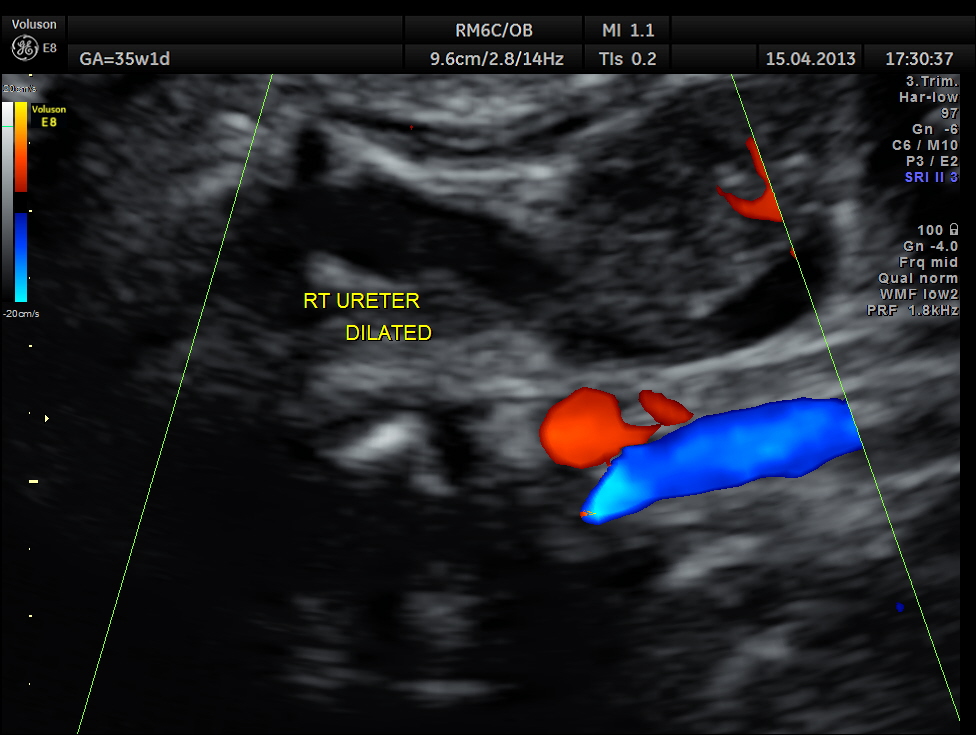

Rt proximal ureter is mildly dilated

Right sided hydro uretero nephrosis , with likely obstruction at right vesico ureteric junction.